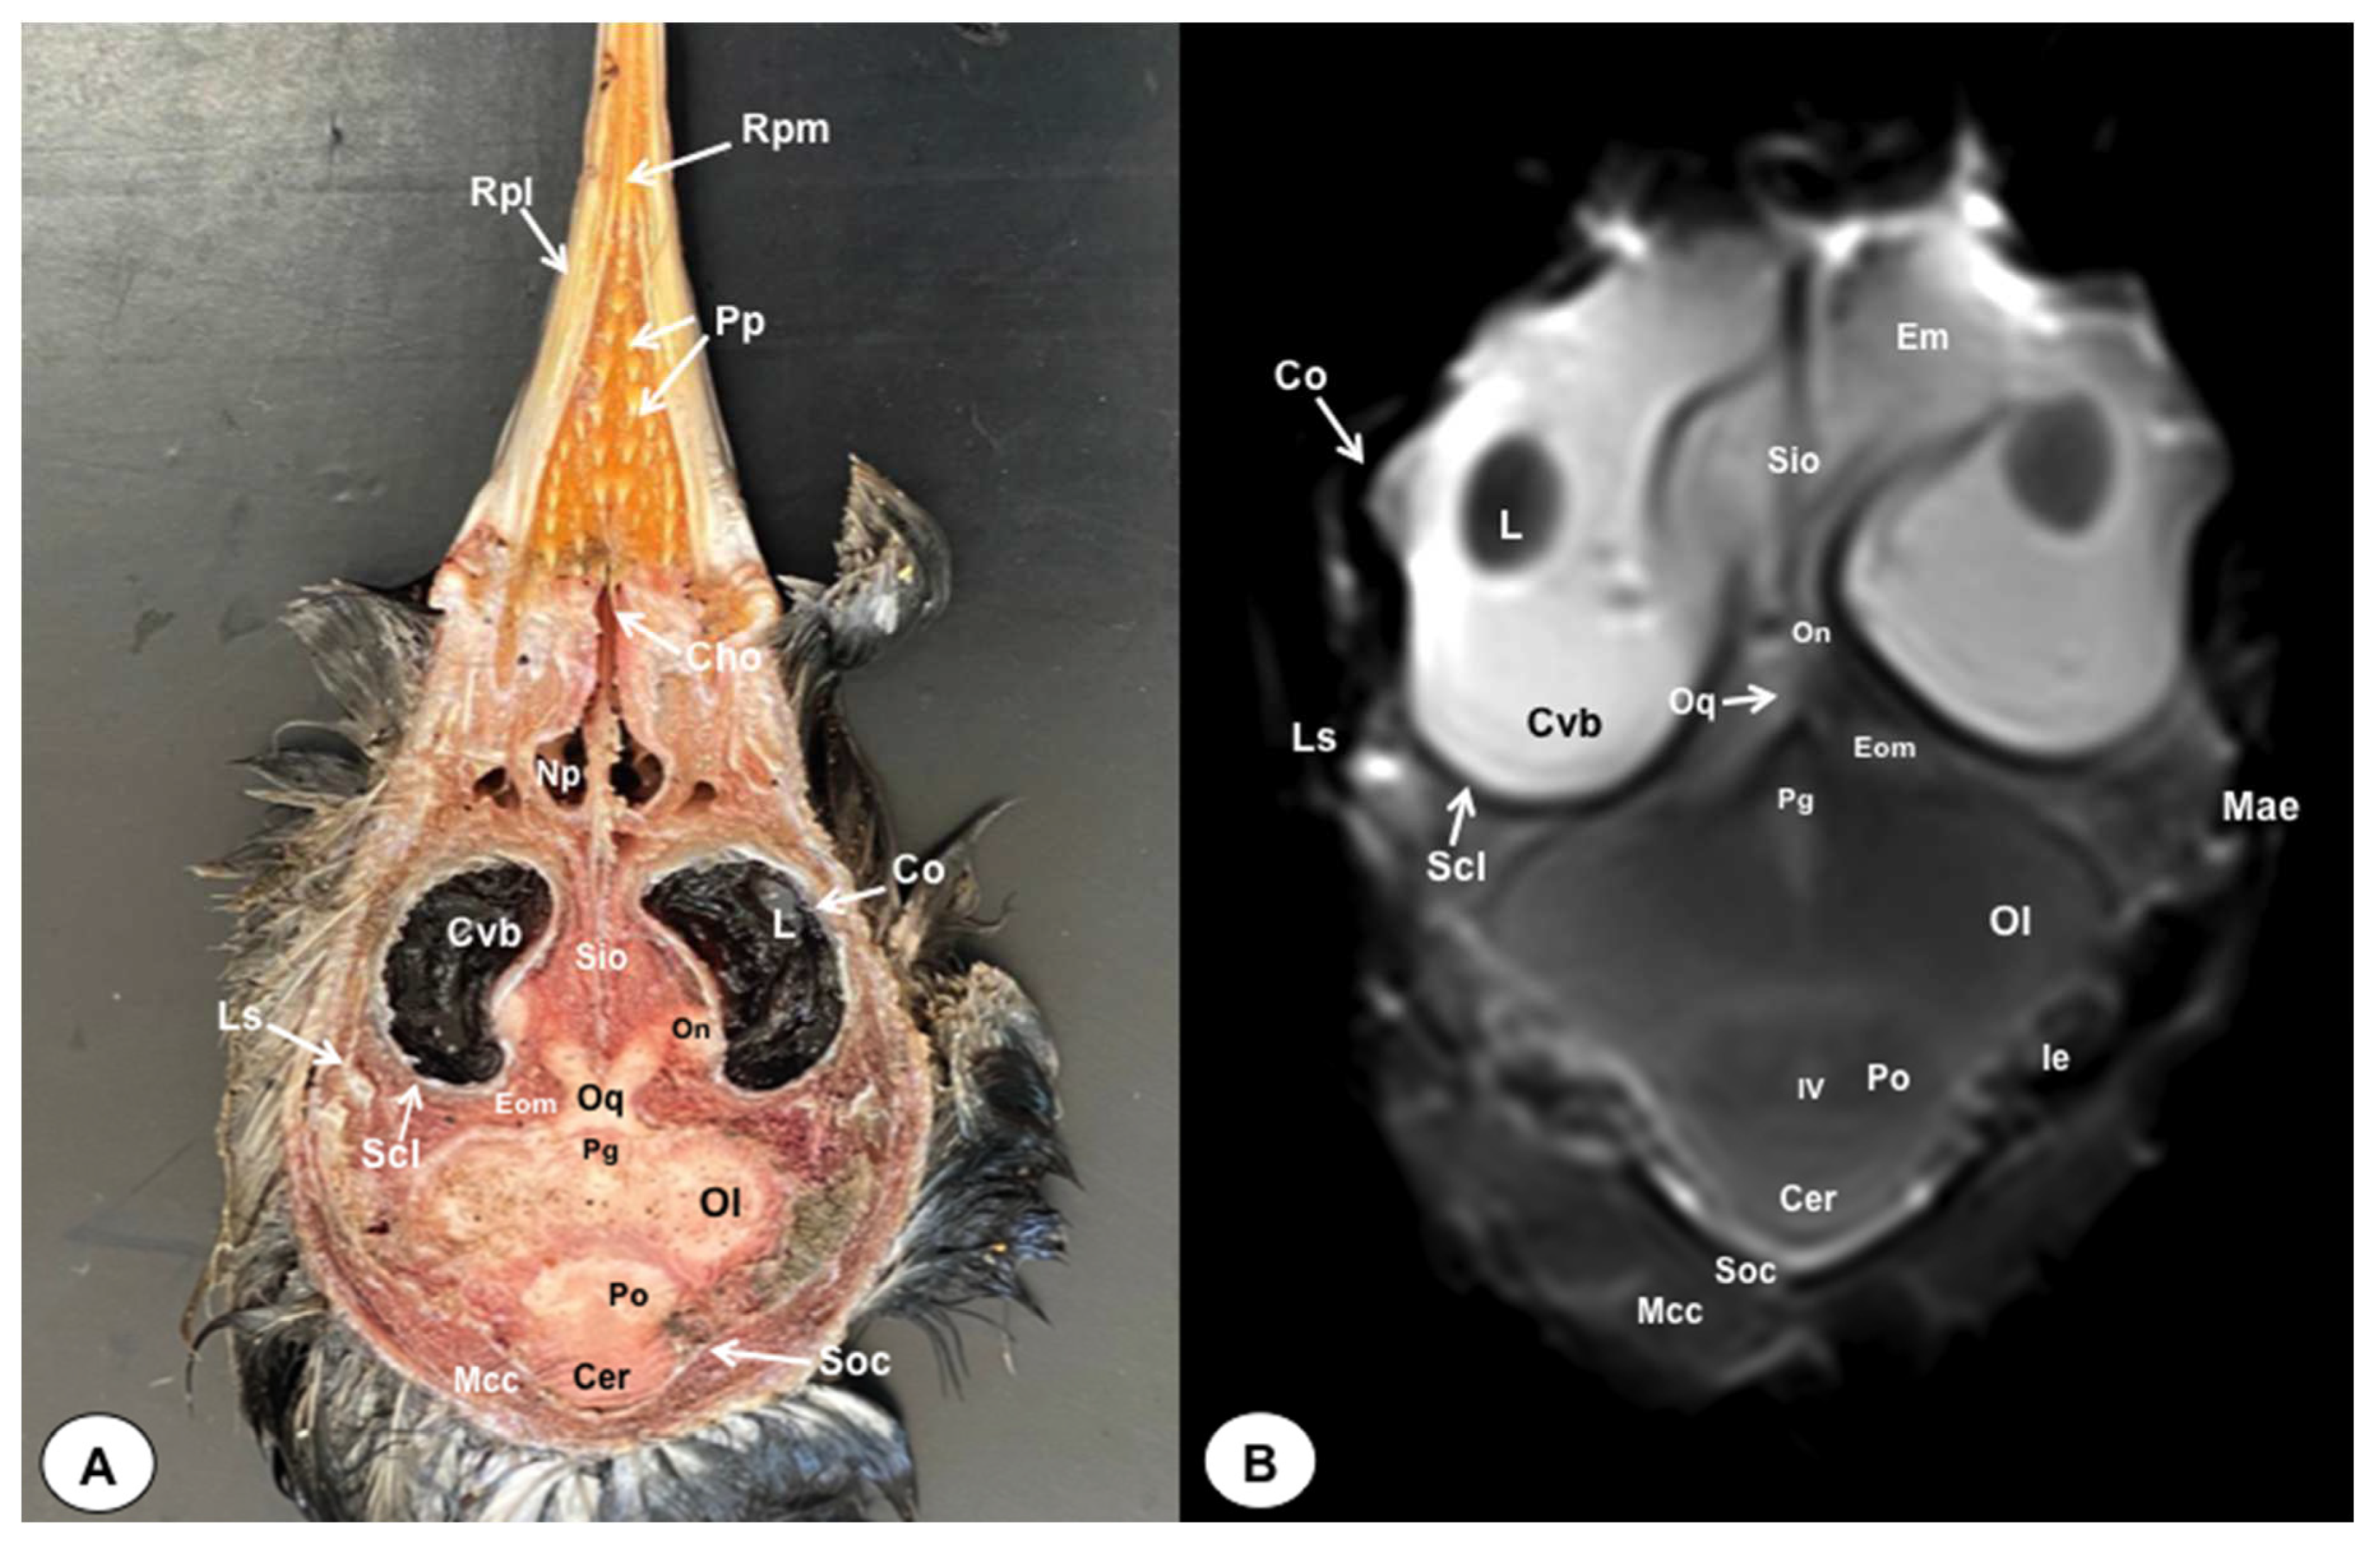

Figure 9. Dorsal cross-section (A) and T2W MR (B) images of the atlantic puffin head at the level of the optic chiasm corresponding to line VIII inFigure 1. Cvb: camera vitrea bulbi; Sio: septum interorbitalis; On: optic nerve; Oq: chiasma opticum; Co: cornea; L: lens; Scl: sclera; Eom: extraocular muscle; Ls: Os laterosphenoidale; Soc: Os supraoccipitale; Po: pons; Cer: cerebellum; Ol: optic lobe; Pg: pituitary gland; IV: fourth ventricle; Ie: Inner ear; Mae: Meatus acusticus externus; Mcc: Musculus constrictor colli; Np: nasopharynx; Em: Musculus ethmomandibularis; Cho: Choanas; Pp: Papillae palatinae; Rpl: Ruga palatina lateralis; Rpm: Ruga palatina mediana.